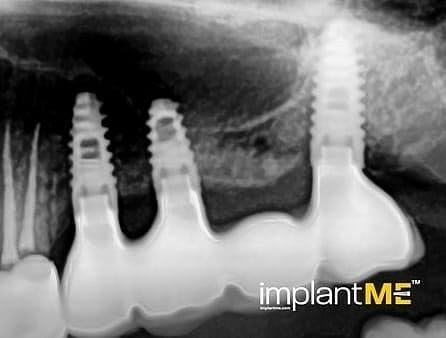

Τα ελκυστικά και ιδιαίτερα υγιή δόντια δεν είναι μόνο καθοριστικό μέρος της εμφάνισής μας, αλλά και της προσωπικότητάς μας. Παλαιότερα, η απώλεια ενός ή περισσοτέρων δοντιών είχε καθοριστικό αντίκτυπο στον τρόπο εμφάνισης των ανθρώπων. Λόγω της σύγχρονης στοματικής εμφυτευματολογίας, αυτό δεν συμβαίνει πλέον. Με συγκριτικά μικρές χειρουργικές επεμβάσεις από το στόμα, μεμονωμένα ή όλα τα ελλείποντα δόντια μπορούν να αντικατασταθούν από εμφυτεύματα, αισθητικά και λειτουργικά ίσα με τα φυσικά δόντια. Μέσω της εισαγωγής εμφυτευμάτων που σχηματίζονται σε ρίζα, είναι δυνατόν να αποφευχθούν αλλοιώσεις των γειτονικών δοντιών και να αγκυρωθούν στεφάνες που δύσκολα διακρίνονται από τα πραγματικά δόντια στα κενά των δοντιών. Οι στεφάνες ή οι γέφυρες που υποστηρίζονται από εμφύτευμα στερεώνονται στα εμφυτεύματα που είναι αγκυροβολημένα στο οστό, γεγονός που δίνει στους ασθενείς μια αίσθηση μάσησης σχεδόν διακριτή από τα δόντια τους. Σε περίπτωση πλήρους έλλειψης δοντιών, τα εμφυτεύματα μπορούν να παρέχουν αξιόπιστες αγκυρώσεις για αφαιρούμενα προσθετικά καθώς και για μεγάλες σταθερές γέφυρες.

Τα οδοντικά προσθετικά που υποστηρίζονται από εμφύτευμα βρίσκονται όσο πιο κοντά μπορείτε να φτάσετε στα φυσικά δόντια. Τα στεφάνια των εμφυτευμάτων βαθμολογούνται με τη φυσική τους εμφάνιση, τα εμφυτεύματα με τη σταθερότητα τους και και τα δύο με τη θετική τους επίδραση στη λειτουργική συντήρηση ολόκληρης της μαστιχικής συσκευής.